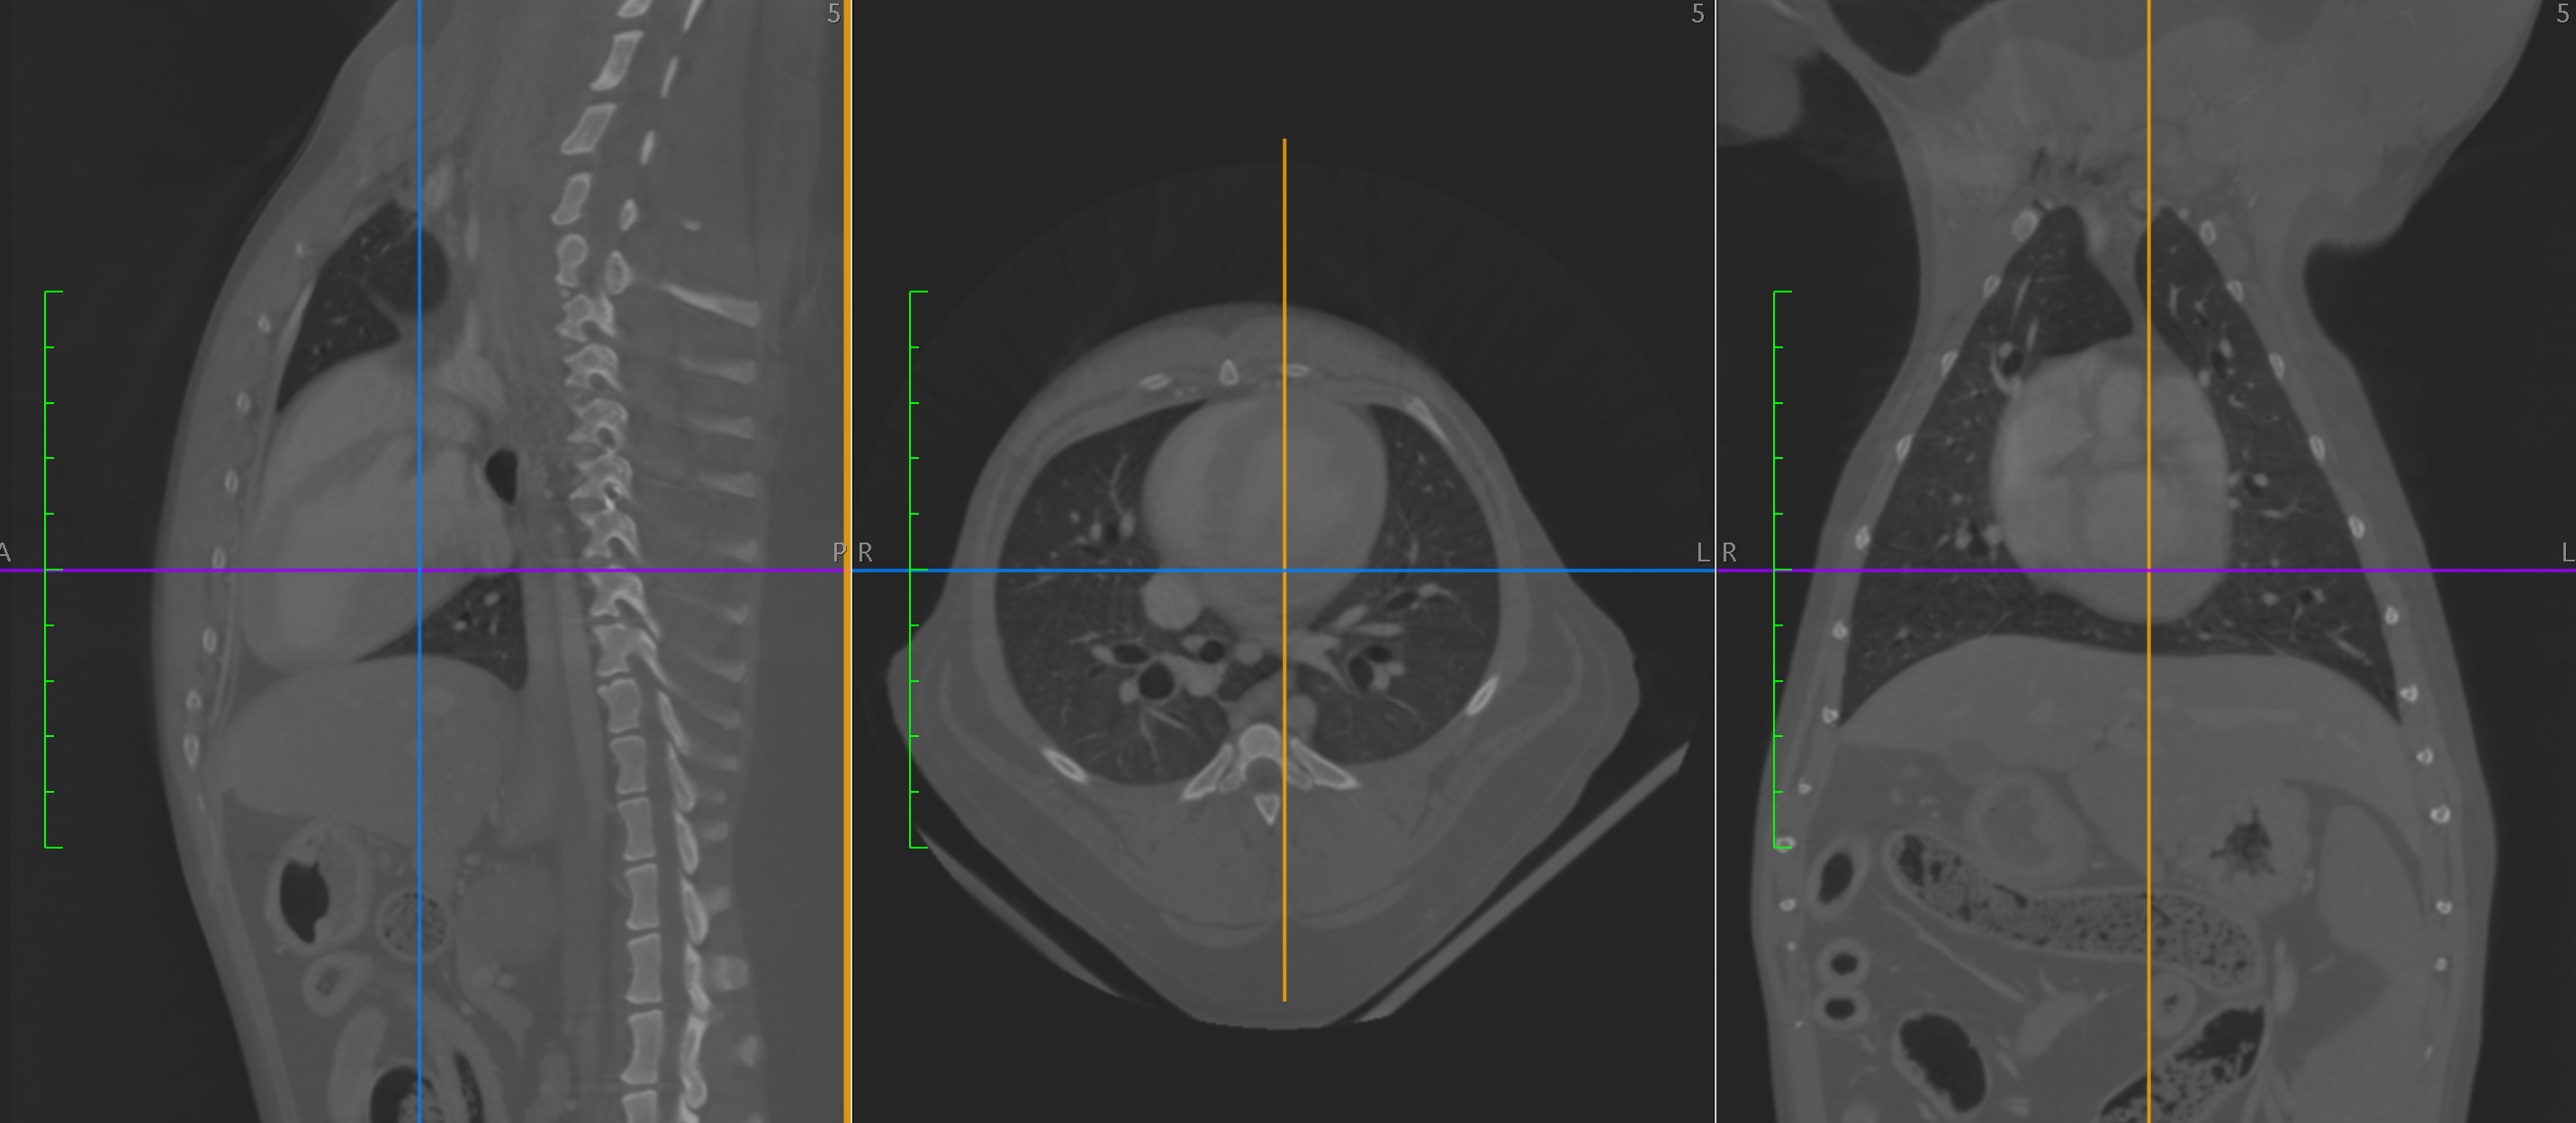

Standiford Veterinary Center strives to provide our patients with the highest level of care. One of the many advanced medical services provided is Computed Tomography or CT scan. CT takes numerous thin “slices” (or X-rays) of the area of interest and then reconstructs the data mathematically into a highly sophisticated and detailed 3-D representation. This scan can be rotated allowing the bones, soft tissue, and vascular structures to be isolated and individually evaluated. Contrast media can be included to markedly improve imaging accuracy and sensitivity.

Most patients are referred for advanced CT imaging when routine diagnostics such as ultrasound or radiographs cannot accurately provide the information needed for a diagnosis or prognosis. CT is exceptional in detecting changes in bones, joints, and cavities or sinuses in the head including the inner ear. The CT also visualizes the spine, chest, lungs, and abdomen. Again contrast agents can provide a detailed map of the blood flow to particular areas such as the liver.